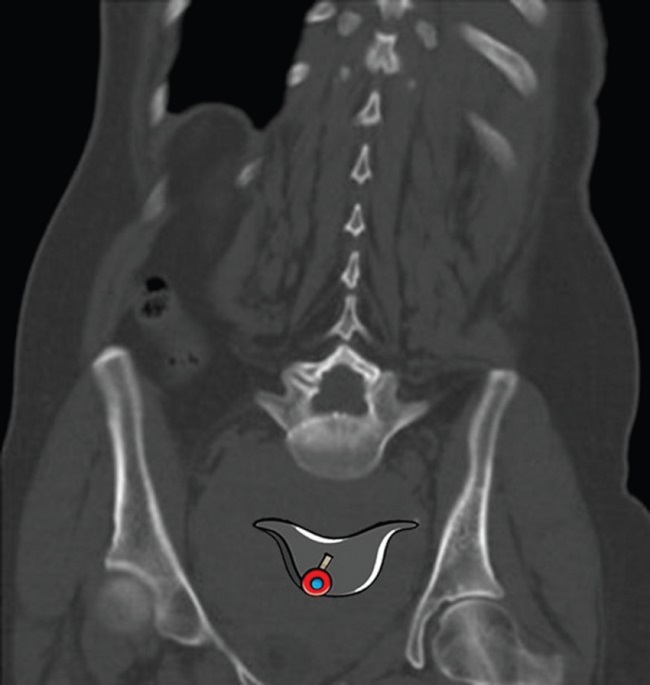

Los hallazgos radiológicos mencionados también se pueden valorar con tomografía computada (TC). La listesis y la espondiloptosis se objetivan de modo sencillo en los cortes sagitales, permitiendo evaluar el grado de desplazamiento del cuerpo vertebral para su clasificación. También es posible visualizar el signo del sombrero de Napoleón invertido en la TC observando la cúpula del sombrero como L5 caída sobre S1 (Fig. 3).

La visualización del signo del sombrero invertido de Napoleón denota espondilolistesis grave o espondiloptosis de L5 sobre S1. Es importante reconocerlo, ya que se puede hallar incidentalmente en radiografías de frente de columna lumbosacra solicitadas por otro motivo, sin siquiera sospechar esta afección, y acompañarla de la incidencia de perfil para confirmar el desplazamiento del cuerpo vertebral.